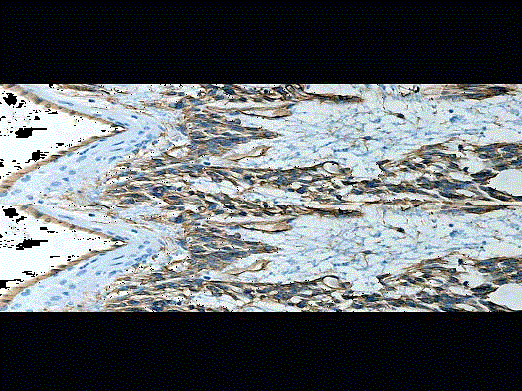

问题 男性,68岁,发现会阴部肿块4月余伴排尿困难,手术切除,大体见结节、分叶状肿块14cm×11cm×5cm,有包膜,切面灰红,鱼肉状,质嫩。显微镜下见肿瘤细胞梭形,束状排列,束间组织疏松(如图);血管丰富,核分裂可见34个/50HPF,免疫组化CD34(+)(如图),Vim(+),CD99(+),Des(-),SMA(-),S-100(-),CK(-),应诊断为 ( )

选项 A.前列腺孤立性纤维性肿瘤 B.前列腺良性增生 C.前列腺平滑肌瘤 D.前列腺纤维瘤 E.前列腺纤维组织细胞瘤

答案 A